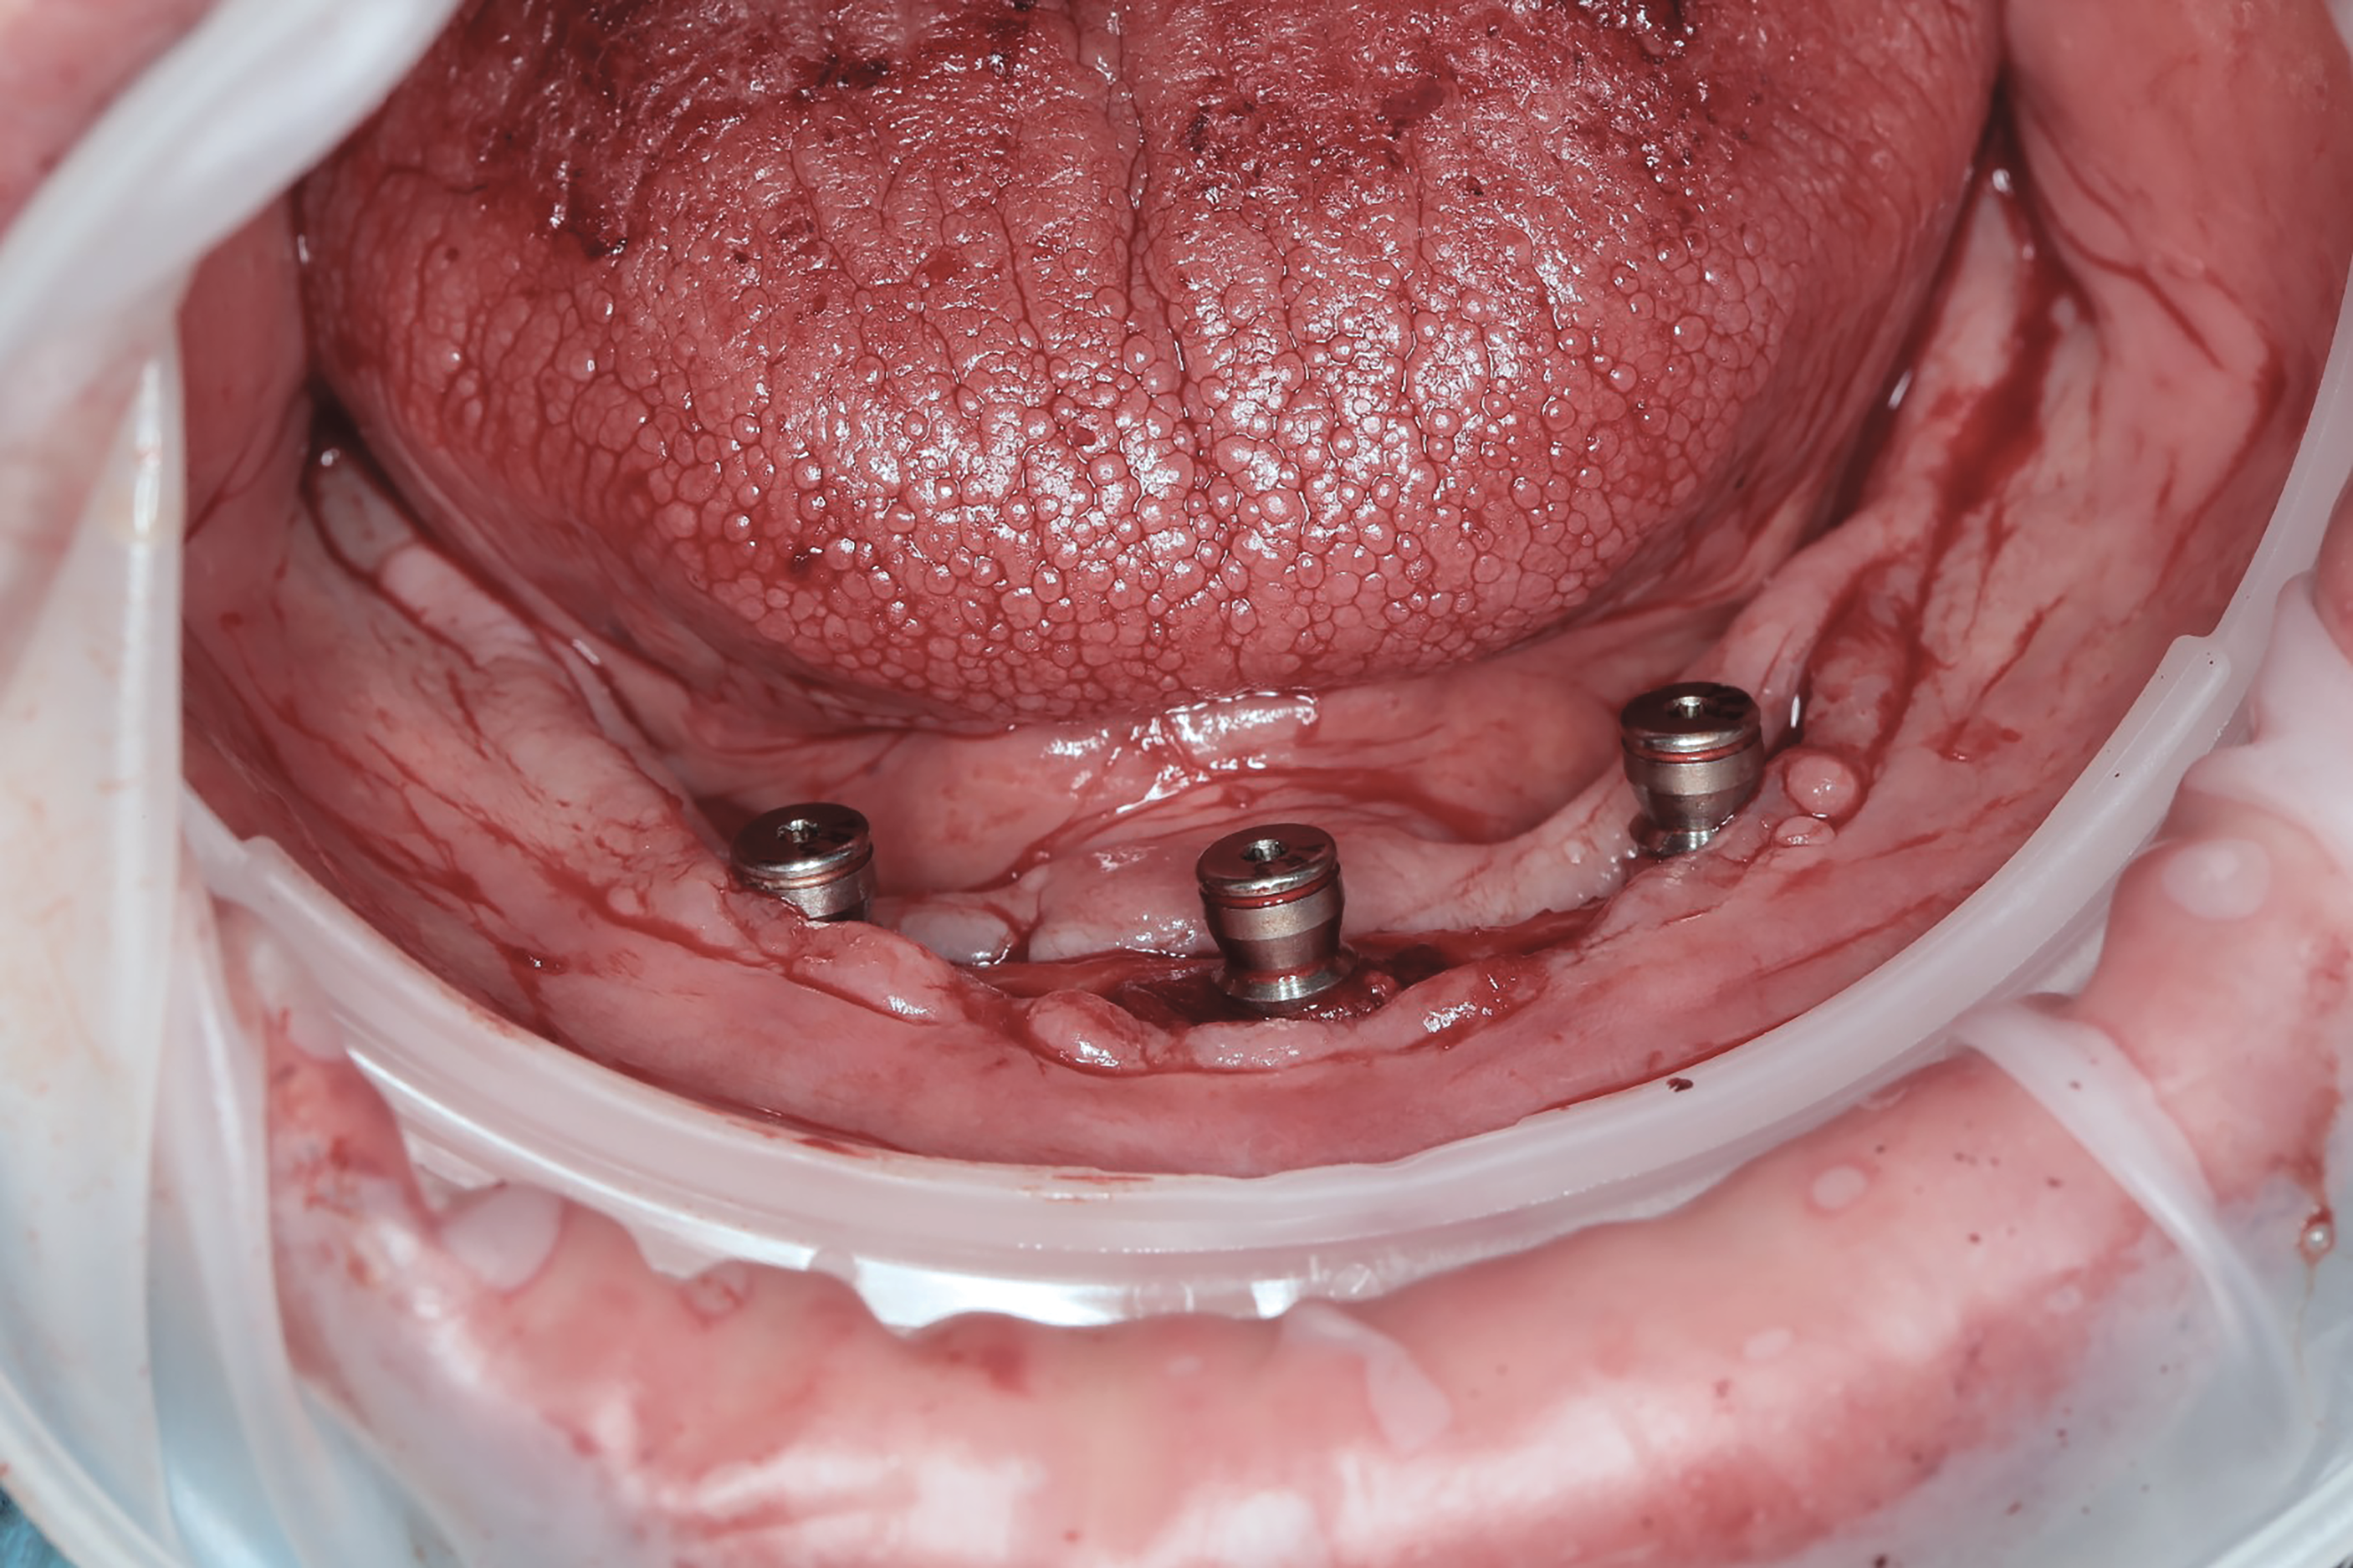

Implants were placed in sites Nos. 27 and 22 (3.8 mm x 9 mm) and site No. 24 (3.8 mm x 10.5 mm). At the 3-month follow-up appointment, all implants were well osseointegrated clinically and radiographically (Figure 6 and Figure 7) with no atypical or pathological findings, and the patient was referred to the denturist for prosthetic rehabilitation.

Fig 6. (Case study 2) Intraoral view of implants following placement of locator-type attachments (3-month follow-up). Clinically healthy gingiva was present with no signs of looming tumor growth.

Figure 6